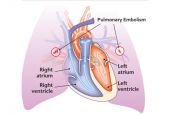

Nếu vách liên nhĩ không tự đóng được, sẽ gây ra bệnh thông liên nhĩ. Thông liên nhĩ lỗ thứ hai là một trong bốn thể của thông liên nhĩ. Để theo dõi rõ hơn về hội chứng Trục điện tim lệch phải ở bệnh nhân thông liên nhĩ lỗ thứ hai, mời các bạn cùng tham khảo bài viết sau đây!

Hình thức hiếm gặp nhất của thông liên nhĩ là thể xoang vành, khuyết tật nơi dự kiến của lỗ xoang vành thường liên kết với hiện diện của tĩnh mạch chủ trên trái đổ về xoang vành. Để hiểu rõ hơn về hội chứng này, mời các bạn tham khảo bài viết dưới đây!

Dextrocardia là khuyết tật bẩm sinh, trong đó tim nằm ở phía bên phải của cơ thể. Có hai loại chính của dextrocardia: dextrocardia of embryonic arrest và dextrocardia situs inversus. Để hiểu rõ hơn về hội chứng này, mời các bạn tham khảo trong bài viết dưới đây!

Thuyên tắc phổi là tình trạng tắc động mạch phổi thường do huyết khối từ hệ tĩnh mạch sâu chi dưới. Vậy trên điện tâm đồ, thuyên tắc phổi lớn thể hiện như thế nào? Mời các bạn tham khảo bài viết dưới đây để hiểu rõ hơn nhé!